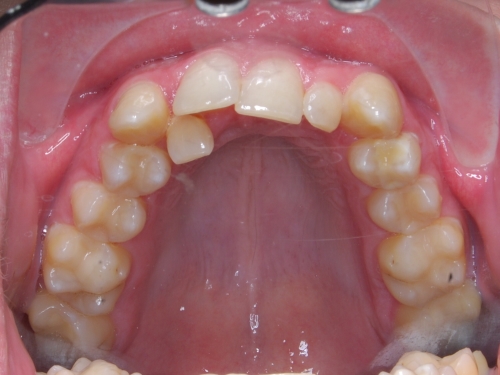

V naší ordinaci používáme kvalitní samoligovací zámky v kovovém provedení. U moderních, samoligovacích zámků dochází k nižšímu tření mezi zámkem a drátem než u zámků s gumičkami, což zjednodušuje léčbu a může jí zrychlit až o 30%. Malé tření zámků, spolu s dalšími prvky, umožňuje ve většině případů vyrovnání zubů bez nutnosti extrahovat některézuby. Používáme pouze variantu v kovovém provedení. Bílé keramické zámky již nepoužíváme z důvodu poměrně vysokého příplatku, který se v součtu blíží ceně rovnátek foliových, která jsou výrazně estetičtější a pohodlnější. Výhody samoligovacích zámků oproti klasickým zámkům s gumičkami:

Při běžné léčbě se snaží lékař dosáhnout zejména perfektního skusu. V této technice je kladen důraz na estetiku úsměvu a obličeje a to nejen v době léčby, ale bere se v potaz i stárnutí obličeje. Tzn., aby úsměv a obličej pacienta vypadal hezky nejen v době léčby, ale také 20 či 30 let po léčbě. Na to je při běžné technice rovnání často zapomínáno. Perfektní skus je samozřejmostí.

Během léčby se snažíme o dosažení širokého úsměvu. Nejen, že je nejhezčí, ale také nejlépe působí proti stárnutí obličeje.

Nejlépe je vidět tento efekt u starších pacientů, u kterých vede vyrovnání zubů touto metodou k výraznému omlazení vzhledu. Ideální počet viditelných zubů (horních) v úsměvu je deset. V Americe preferují dokonce dvanáct. Tomuto trendu jsou nejlépe uzpůsobená fixní rovnátka s použitím samoligovacích zámků a snímatelná foliová rovnátka.